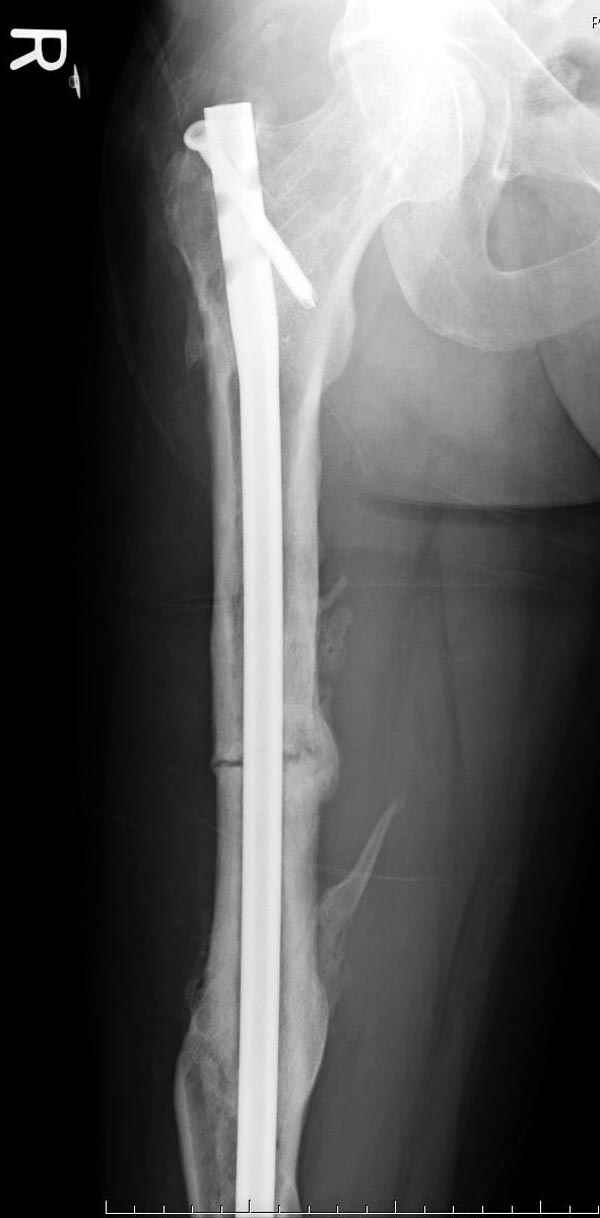

Инфекция канала и стрессовый перелом:

Представляю снимки больного с политравмой: леченного в другом мед.учреждении по поводу открытого перелома бедра, сперва аппаратом наружной фиксации, затем пластиной. Обратился к нам через 8 месяцев после удаления пластины с проблемой несросщего перелома бедренной кости, без клинических проявлении к инфицированию (не все снимки сохранены)

Рутинный интрамедуллярный остеосинтез с расверливанием и с фиксацией реконструктивным трокантерик штифтом (рис №1, №2),

если первые 4 месяца послеоперационного периода проходил без проблем, но на 5 месяце появились боли в дистальном отделе бедра и температура, т.е. симптомы медуллярного инфицирования (рис №3, №4).